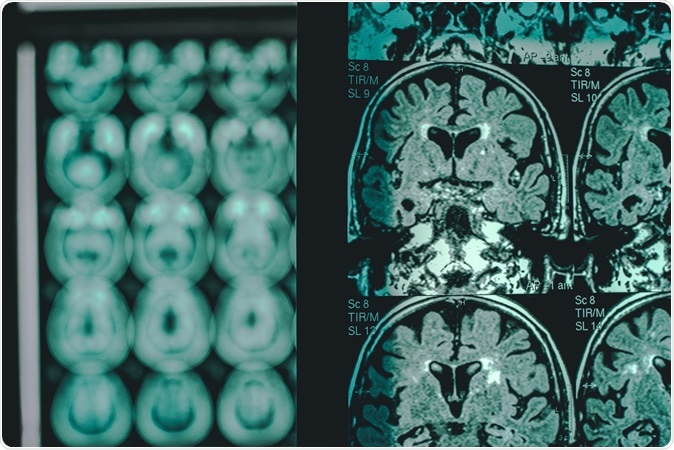

Alzheimer

Alzheimer's disease shown on an MRI scan. Image Credit: Atthapon Raksthaput / Shutterstock